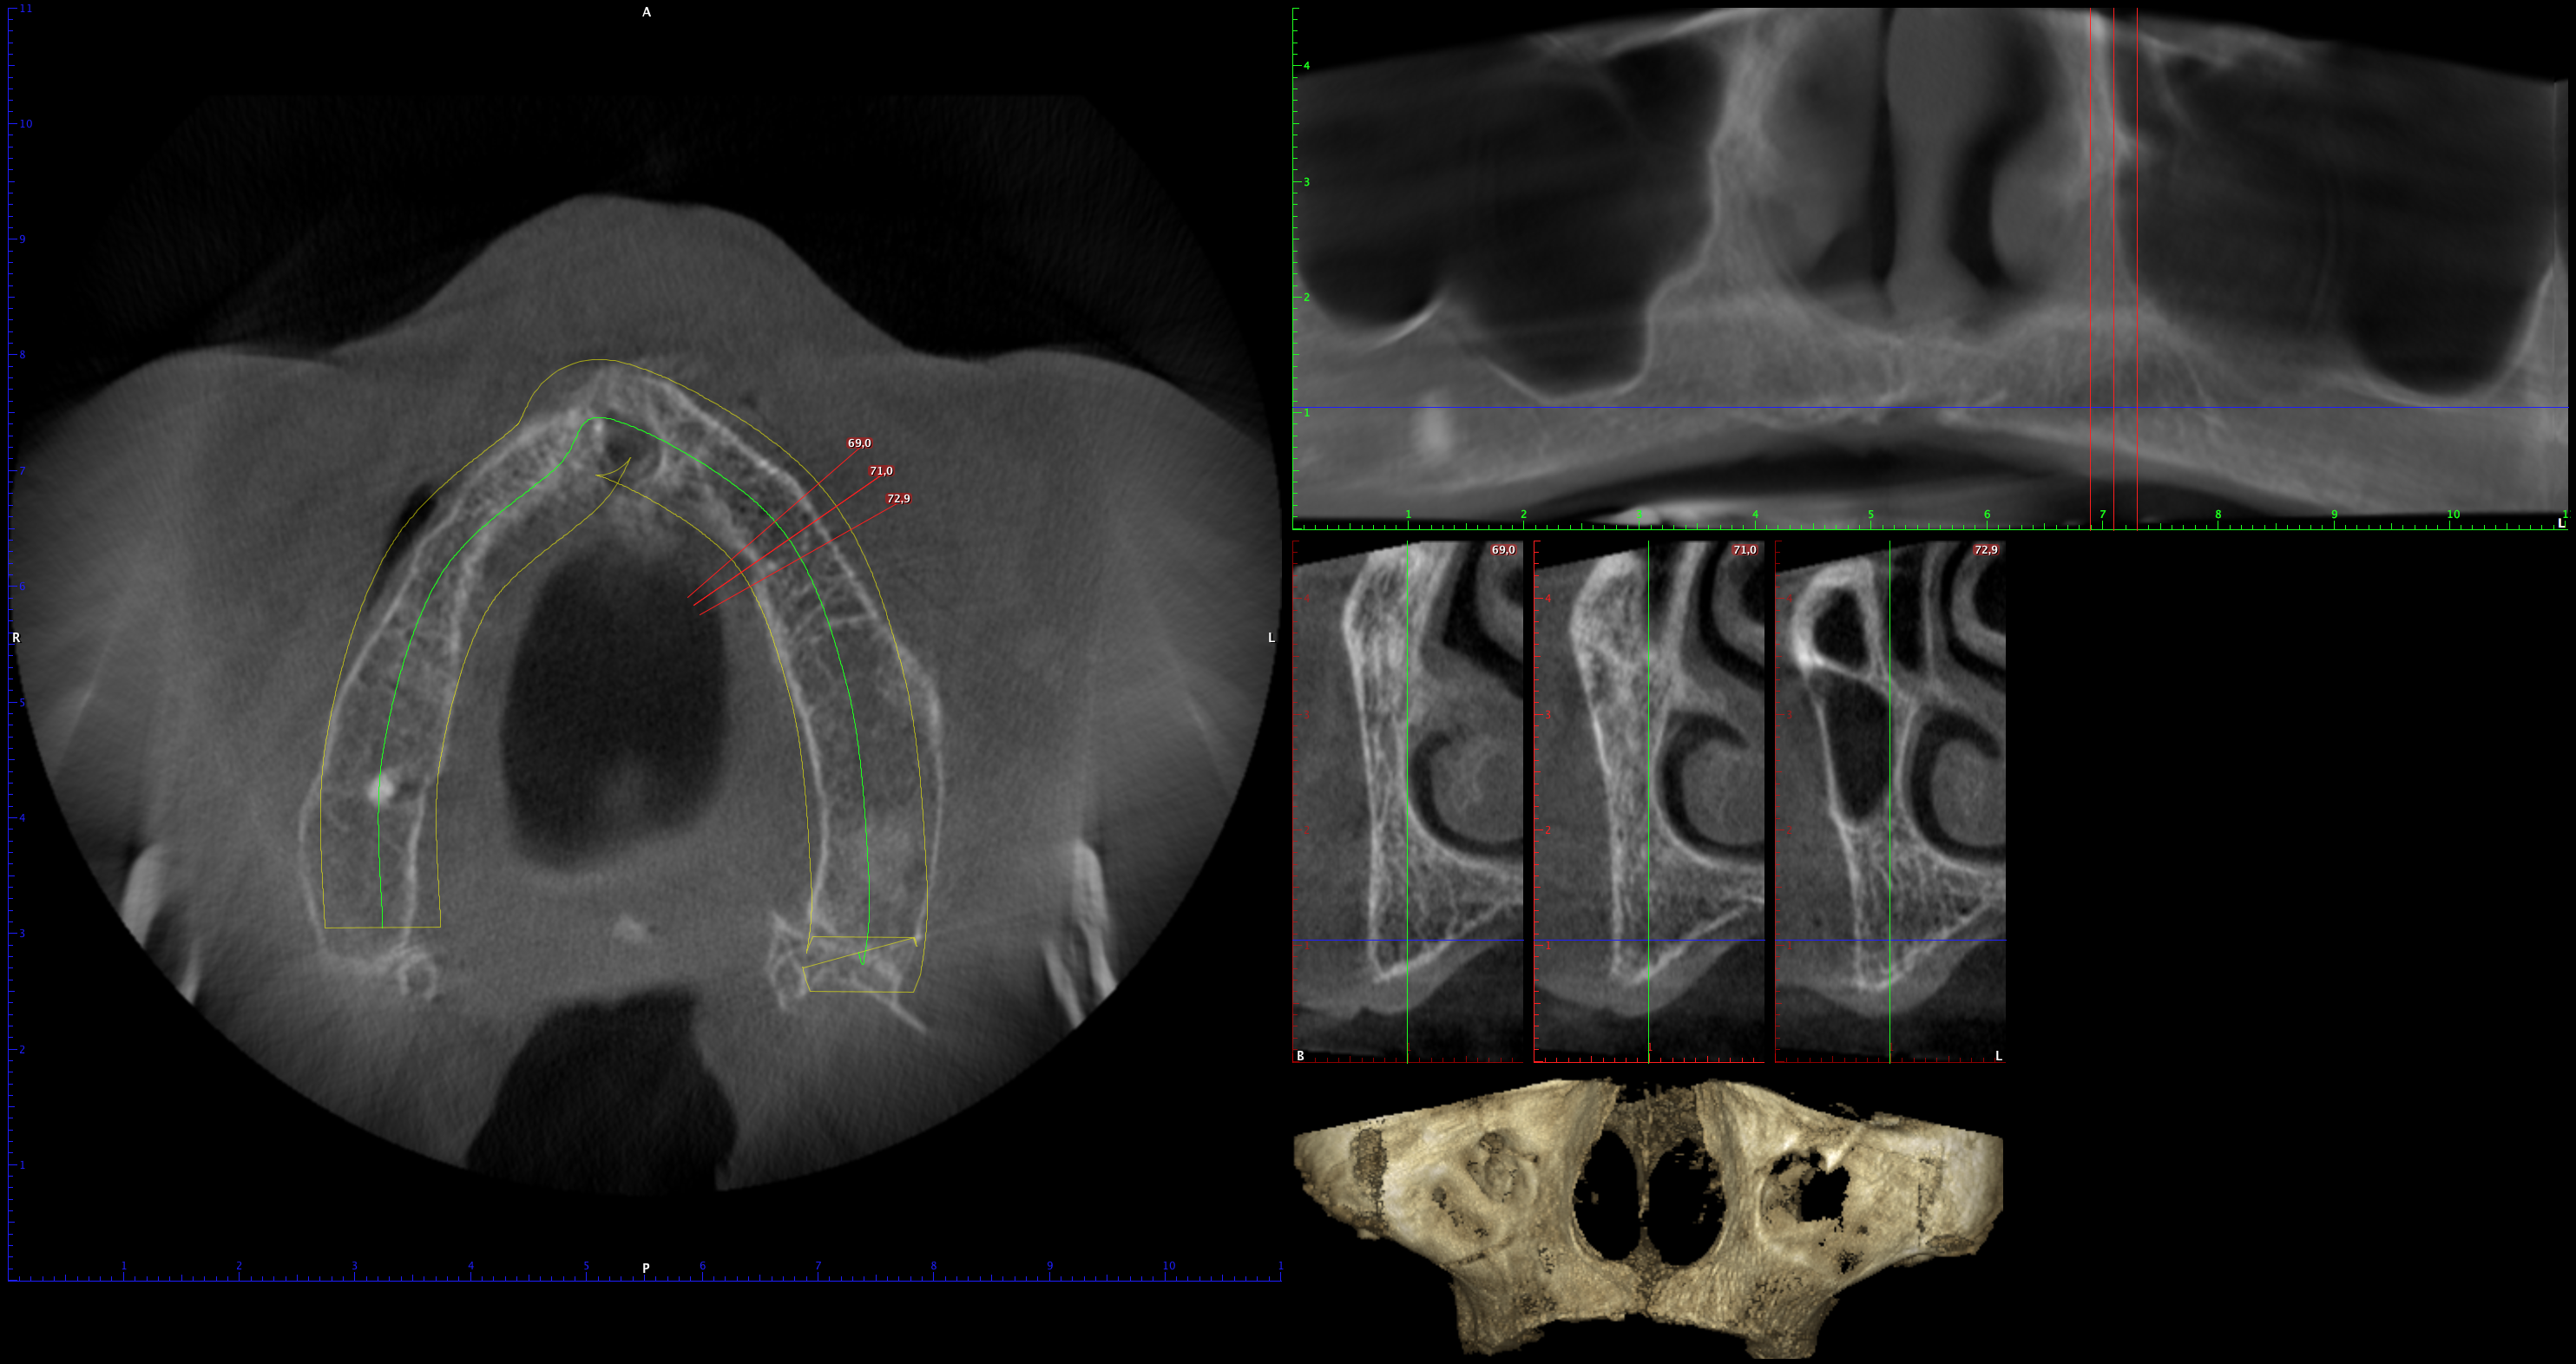

En PROTAC conseguimos una combinación ideal de calidad de imagen y usabilidad de alto nivel, ya que disponemos de una unidad CBCT(Cone Beam Computed Tomography) de última generación que supone un extraordinario avance en la evolución del procesamiento de imágenes de haz cónico, obteniendo una calidad de imagen optimizada, reduciendo los artefactos y garantizando imágenes de mayor contraste, para conseguir así satisfacer las necesidades del exigente procesamiento de imágenes maxilofaciales en todos los entornos clínicos. Nuestro innovador software Planmeca Romexis® ofrece herramientas especialmente diseñadas para especialistas en implantología, endodoncia, periodoncia, prostodoncia, ortodoncia, cirugía maxilofacial y otorrinolaringología.

Nuestra unidad de escáner y radiografía dental y nuestro software de procesamiento de imágenes brinda una combinación innovadora de imágenes 2D y 3D que le ofrecen una visión más completa para conocer con mayor exactitud las necesidades de sus pacientes.

Unidad CBCT de última generación con una calidad de imagen optimizada.

Software con herramientas especializadas para implantología, endodoncia, periodoncia, prostodoncia, ortodoncia, cirugía maxilofacial y otorrinolaringología.

Imágenes 2D y 3D más completas para conocer con mayor exactitud las necesidades de sus pacientes.